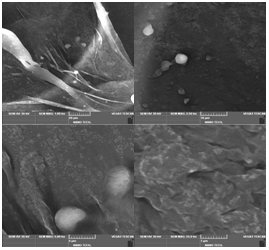

Encapsulation of Phyllanthus Emblica Fruit Extract Biodegarable Gelatin Nanosperes: Design Characterization and In Vitro Antioxidant Assessment

By jeeva .E, P.Santhiya , Dr.M.Amudha , Dr.V.Ganesan